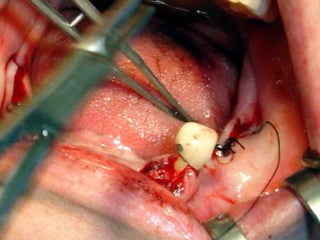

Plastia de maxilares para implantes dentales.

La conformación quirúrgica de un contorno alveolar adecuado es

determinante para la correcta aplicación y aceptación de los implantes

de titanio, aquí proponemos una técinica para lograr el espesor óseo

suficiente y la corrección estética del proceso, ya que antiguamente al

extraer un diente se acostumbraba presionar las tablas alveolares

“para cohibir la hemorragia”, con el colapso subsiguiente de la región.

Incisión

Disección cuidadosa del colgajo

Defecto óseo a corregir

Múltiples perforaciones en hueso compacto

Aspecto de hueso cribado